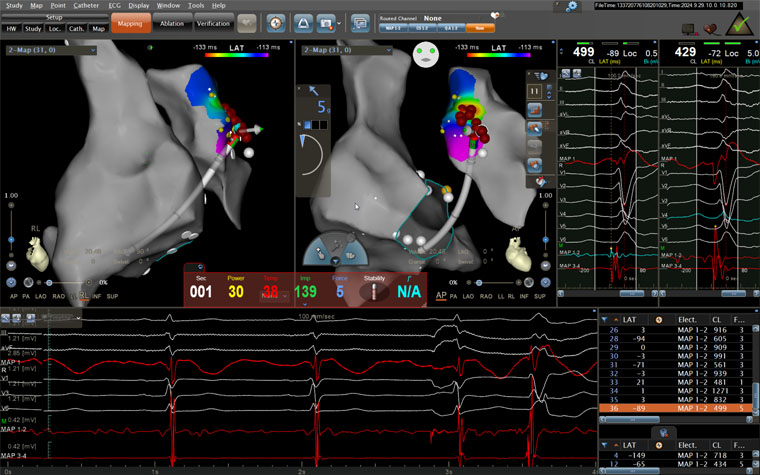

术中患者射频消融情况

手术当日,医护人员连接多导电生理仪和CARTO三维标测系统,对病人进行术前消毒,局麻后穿刺股静脉,操作ST消融导管至右房,建立右心三维解剖。术中,姚铁柱副主任操作ST消融导管经三尖瓣进入右室流出道,于右室流出道后游离壁标测到最早激动靶点,诱发室早形态与原体表心电图室早形态相同,给予放电消融,患者室早消失;继续行冠脉造影术,导管造影结果显示,前降支中段可见约50%局限性狭窄。术毕,患者安返病房,心电图示为“窦律规整”;继续给予心电监测,患者无室早出现,心慌、气短症状消失。根据冠状动脉造影结果对其调节药物治疗,患者胸痛、背痛症状得到缓解。术后仅不到两日,患者便顺利出院。